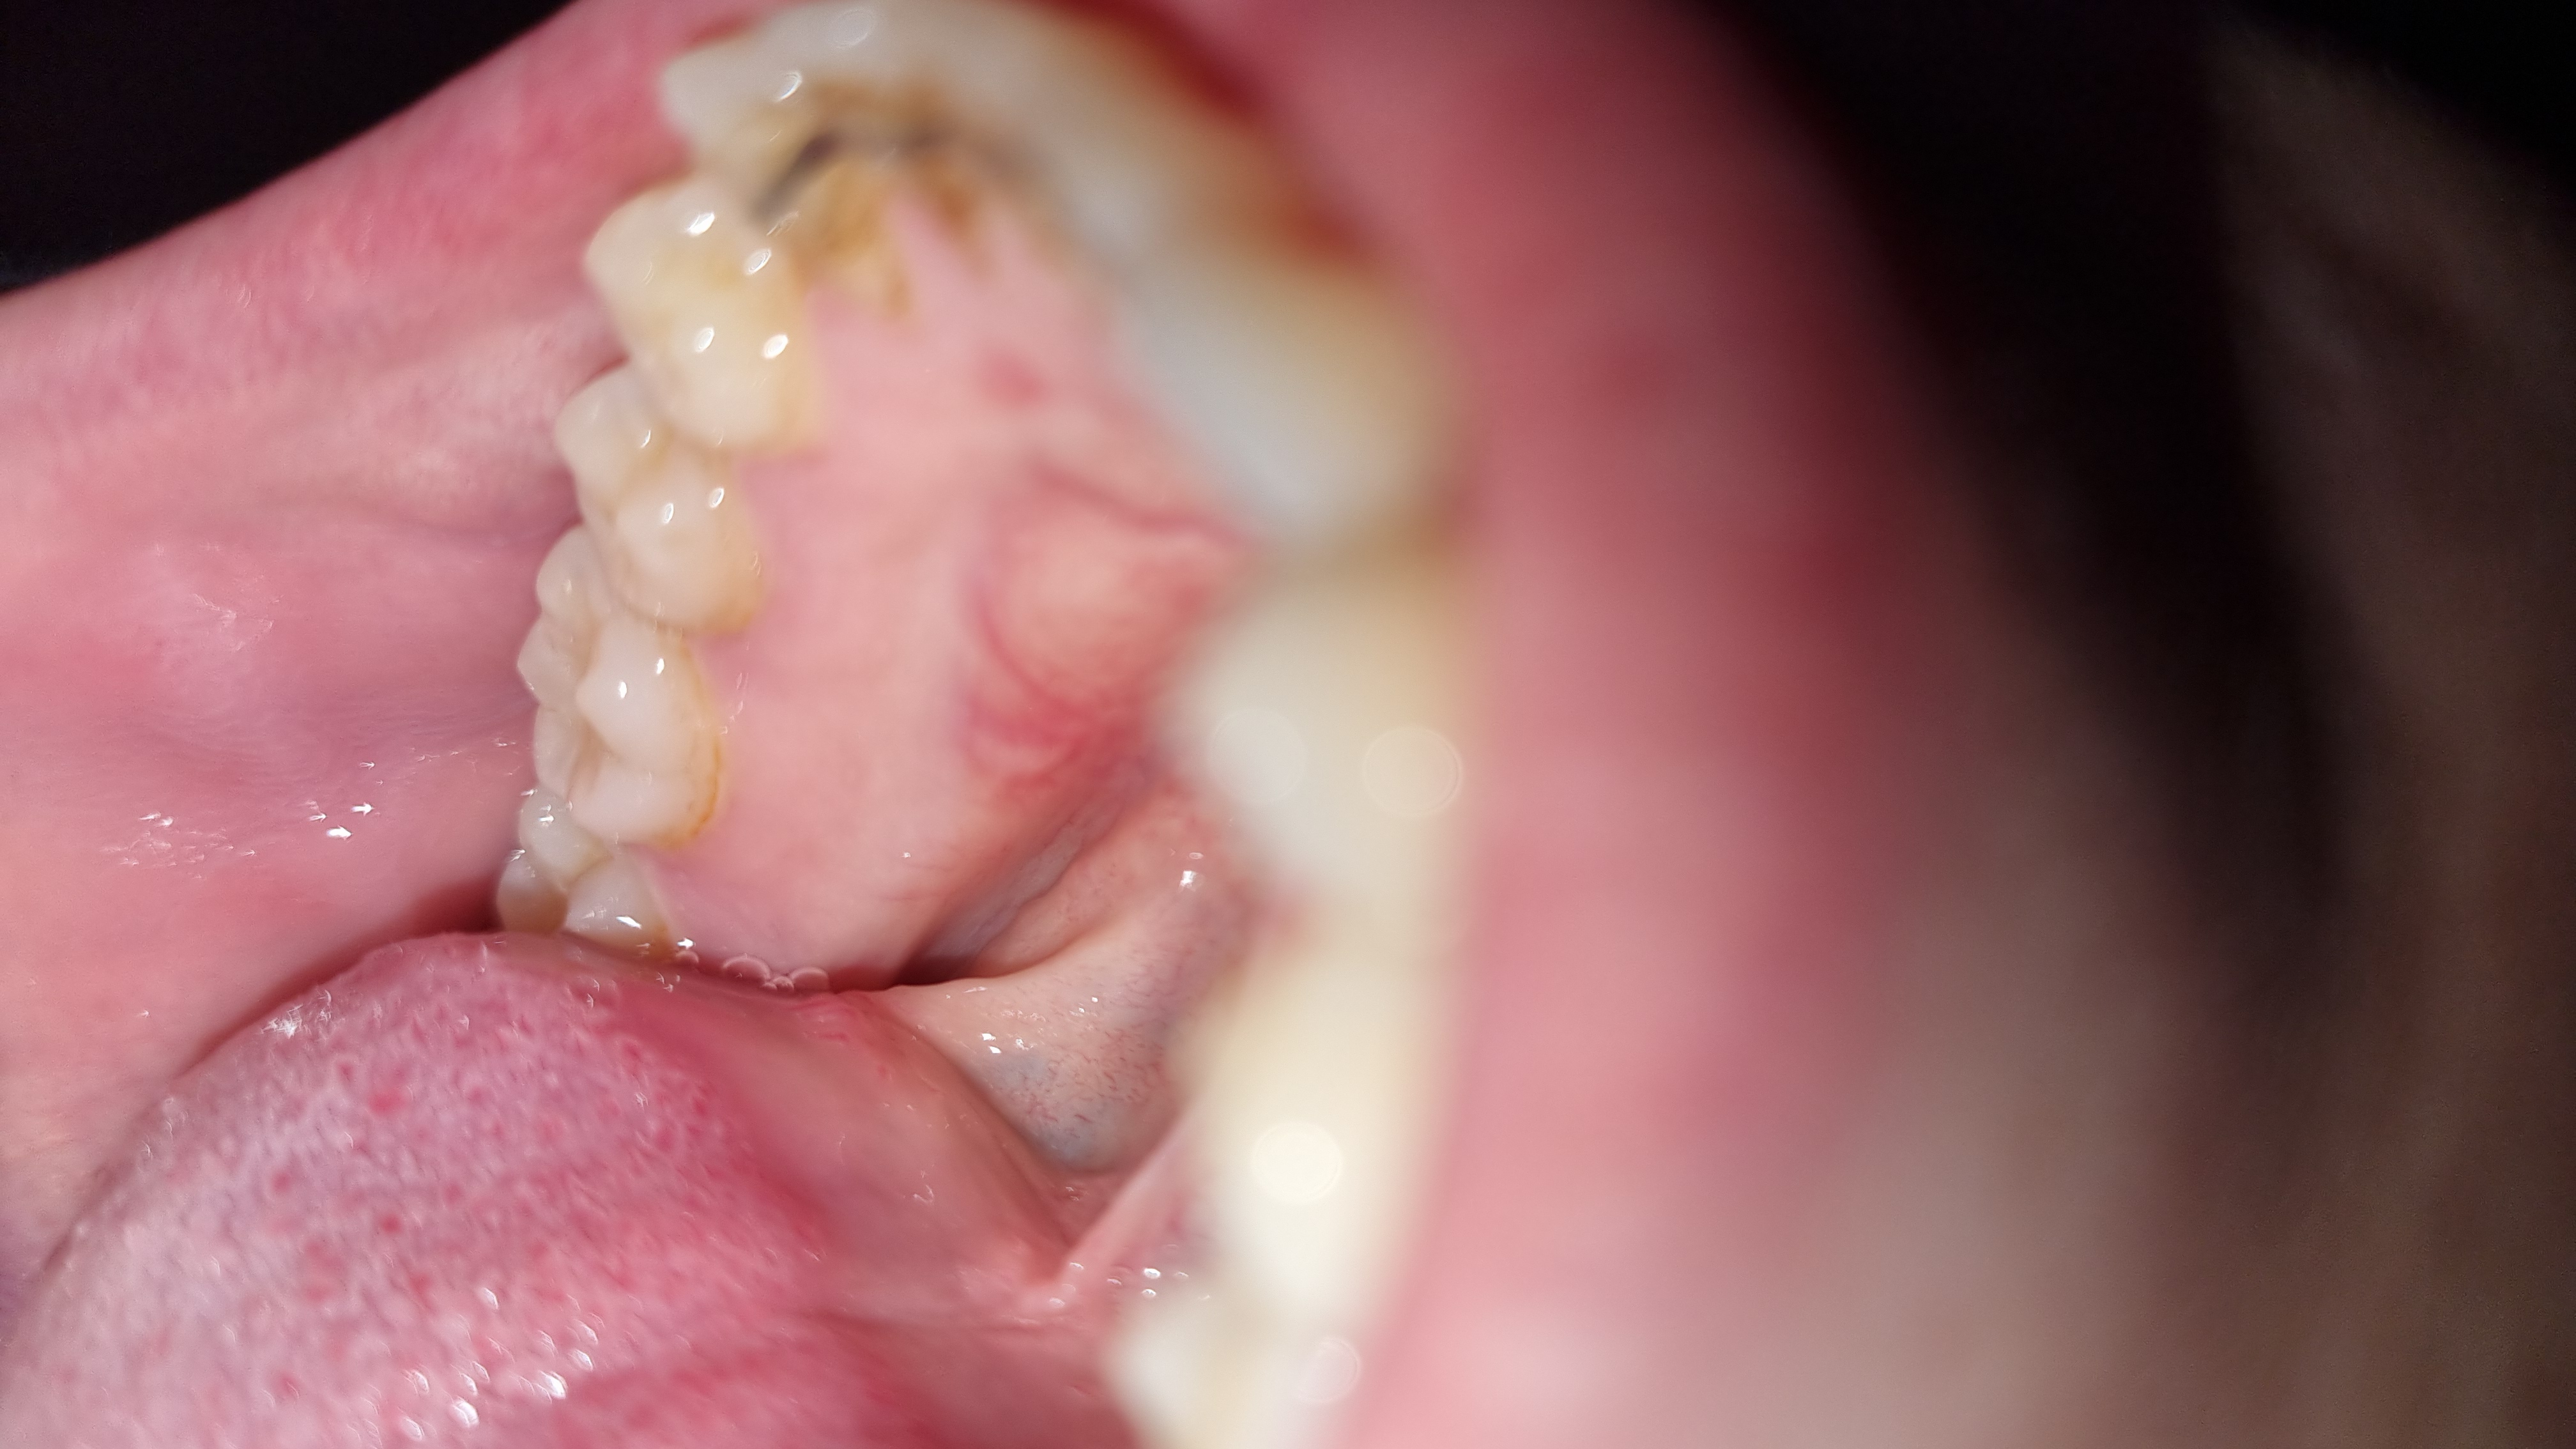

Buongiorno, Sono una ragazza di 25 anni. Da circa un mese ho notato con la lingua un rigonfiamento nel palato inferiore. Appare bianco e arrossato nella zona circostante. Non è dolente se non al tatto è ha una consistenza dura. Non so cosa possa essere e se debba preoccuparmi. Non è cresciuta in questo periodo di tempo. È spuntata da un giorno all'altro.

Assolutamente nulla di preoccuante. Una esostosi ch tutti hanno - se ne è accorta solo ora ma c'è sempre stata. Se qualcosa cambia in un paio di settimane si faccia visitare..

Gentilissima utente le foto non sono affidabili, occorre visita odontoiatrica.